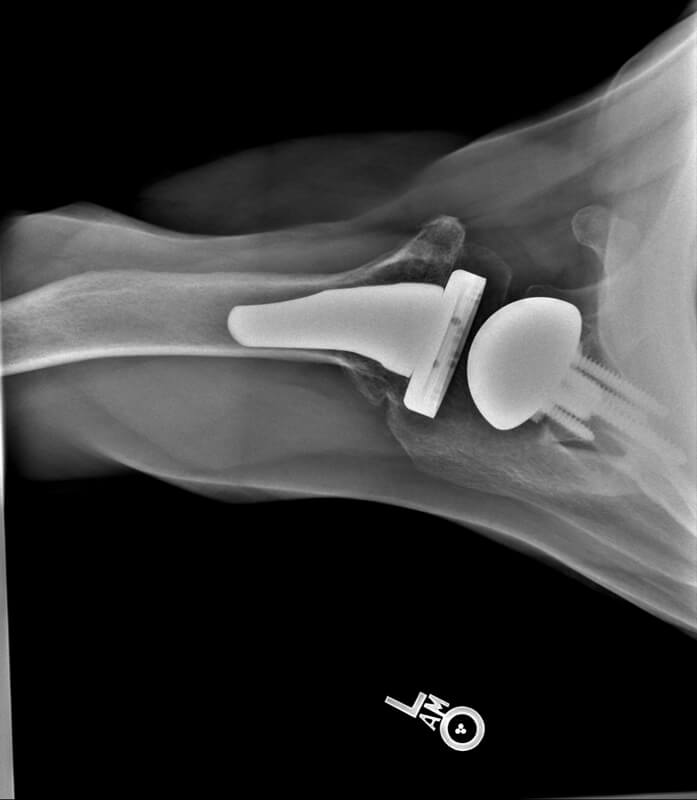

Stryker/Wright/Tornier, Flex Ascend Humerus, Perform Full Wedge Glenoid